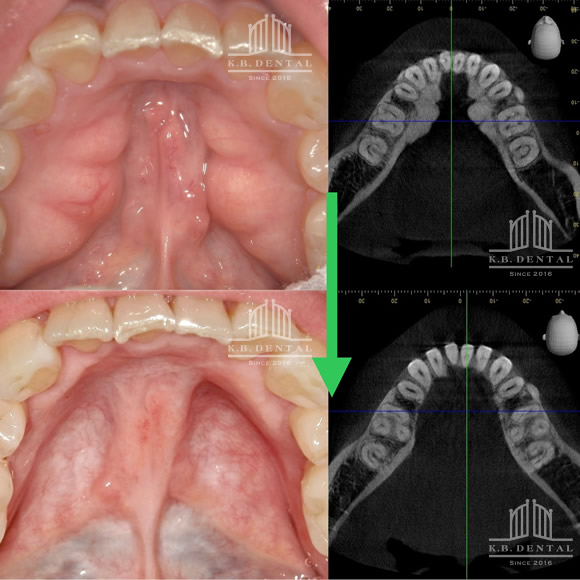

正中過剰埋伏歯(せいちゅうかじょうまいふくし)

正中過剰埋伏歯 症例

正中過剰埋伏歯の症例です。鼻腔底直下にあるので、静脈内鎮静を使い無痛抜歯で対応しました。抜歯が怖い方はご相談下さい。